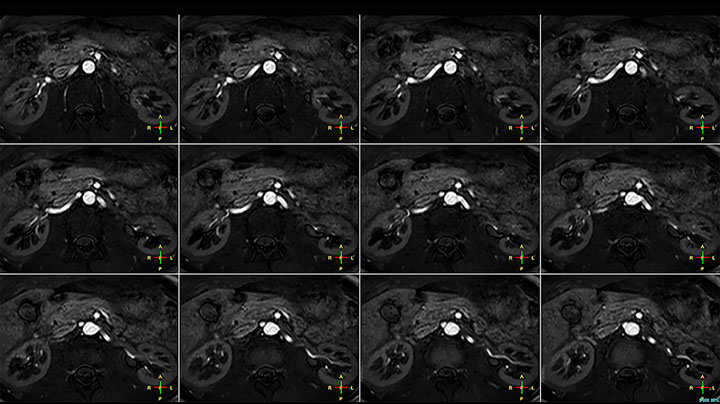

MR-Untersuchung einer 61-jährigen Patientin mit einem malignen Lymphom mit diffusionsgewichteter Ganzkörper-MRT sowie PET. Auf den gezeigten Bildern ist die Auflösung mit der diffusionsgewichteten MRT besser als mit der PET, die eine Darstellung der kleinen Beckenläsionen ermöglicht; im Halsbereich ist praktisch keine Verzerrung zu erkennen.